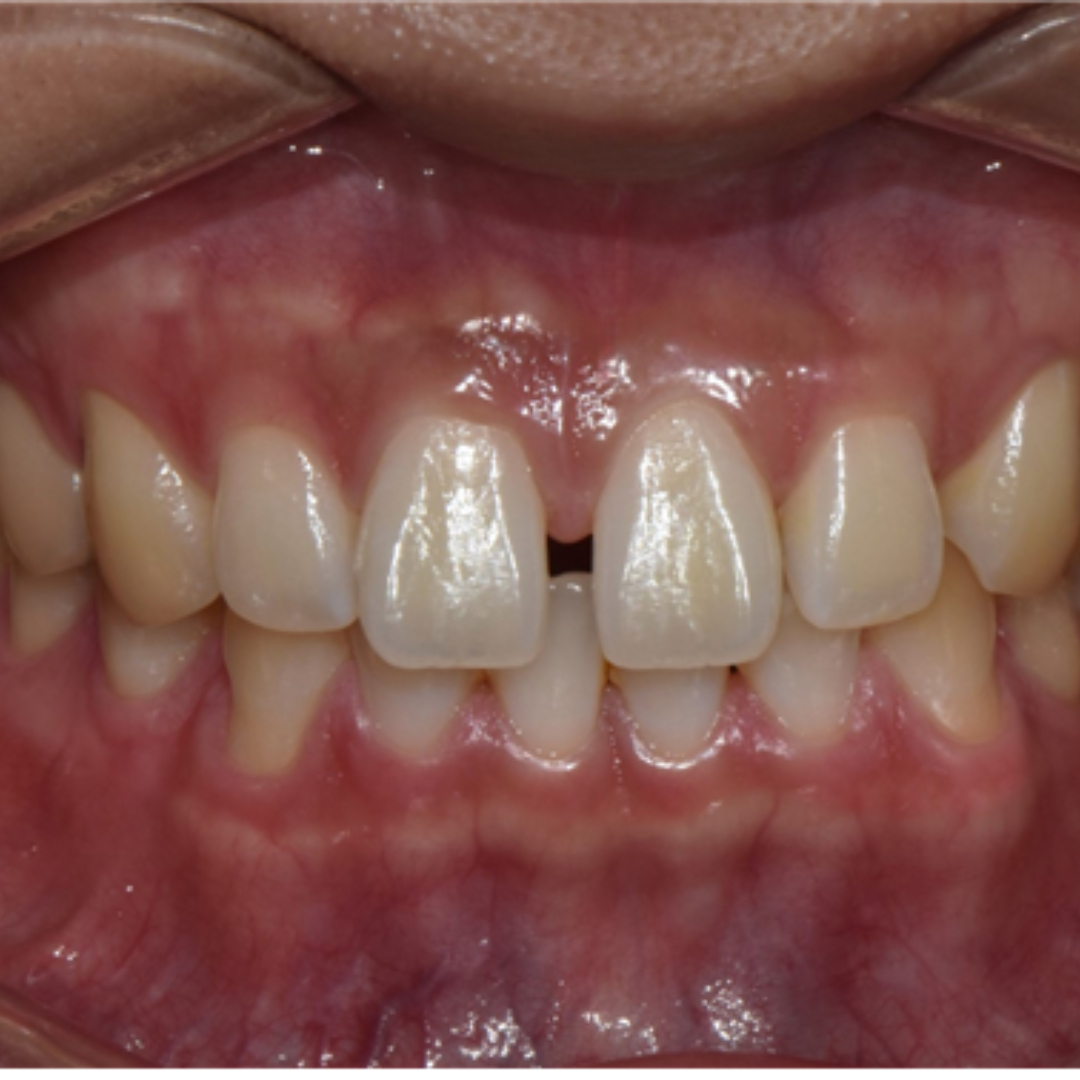

앞니 사이 벌어진 공간과 정중선 불일치를 고민으로 내원하셨던 20대 남성 환자분입니다. 윗니, 아랫니 공간이 각각 3.4mm, 2.6mm 가량 벌어져있고, 위와 아래의 중앙선 차이가 2.1mm 정도로, 상대적으로 정중이개와 정중선 불일치가 눈에 띄는 모습입니다. 해당 환자분께서는 격투기를 취미로 하시는 분이셔서 교정장치를 부착한 채로 얼굴 부위에 타격이 있을 경우 입 안이 다칠까봐 걱정이 있으셨습니다. 교정 진단 상담 후 고민 끝에 부상 방지를 위해 표면이 매끈한 투명교정 장치로 치료하시기로 결정하셨습니다.

최근에는 티 나지 않는 교정을 원하시는 심미적인 이유 뿐만 아니라, 위생 관리, 음식물 섭취, 부상 방지 등 다양한 이유로 전통적인 부착식 교정장치 대신 투명 교정을 선택하시는 환자분들이 부쩍 많아지셨습니다. 투명 교정 치료는 결과는 동일하면서 사진 촬영, 운동, 여행 등 일상 생활에 제약이 크게 없다는 점이 큰 장점입니다. 다만, 증례에 따라 부착식 교정장치가 더 빠르고 효과적인 경우도 있어 교정 치료 전 전문의와의 상담을 통해 결정하는 것이 좋습니다. ^^ 총 32주 간의 교정 치료가 종료된 모습입니다. 기존에 가장 고민이셨던 공간 벌어짐, 정중선 불일치가 예쁘게 수정되었습니다. 2025.5.18.

치료 전, 후 미소가 눈에 띄게 개선되었습니다. 정면에서 두드러지게 보였던 정중 이개와 정중선 불일치가, 벌어진 공간이 폐쇄되고 가지런하게 배열되니 깔끔하고 정돈된 인상을 줍니다. 앞니의 벌어진 공간 폐쇄를 위해 라미네이트나 크라운 치료로 심미적이고 즉각적인 개선을 가져오는 경우도 있습니다. 하지만 위 환자분의 경우 다른 부정교합이 있기 때문에 교정 치료 없이 심미 보철을 진행했다면, 정중선 불일치가 잔존하거나, 앞니 크기가 비대칭적으로 마무리되었을 수 있습니다. 32주의 교정 치료로 자연스럽고 아름다운 미소를 회복하여 환자분도, 의료진도 만족한 결과를 얻어 성공적인 투명 교정 치료 증례로 소개드렸습니다. 세심한 진단과 맞춤형 치료계획으로 예쁜 미소를 찾아드립니다! 안전한 365서울앞선치과 교정 치료 많은 관심 부탁드립니다~!!

치료 전, 후 미소가 눈에 띄게 개선되었습니다. 정면에서 두드러지게 보였던 정중 이개와 정중선 불일치가, 벌어진 공간이 폐쇄되고 가지런하게 배열되니 깔끔하고 정돈된 인상을 줍니다. 앞니의 벌어진 공간 폐쇄를 위해 라미네이트나 크라운 치료로 심미적이고 즉각적인 개선을 가져오는 경우도 있습니다. 하지만 위 환자분의 경우 다른 부정교합이 있기 때문에 교정 치료 없이 심미 보철을 진행했다면, 정중선 불일치가 잔존하거나, 앞니 크기가 비대칭적으로 마무리되었을 수 있습니다. 32주의 교정 치료로 자연스럽고 아름다운 미소를 회복하여 환자분도, 의료진도 만족한 결과를 얻어 성공적인 투명 교정 치료 증례로 소개드렸습니다. 세심한 진단과 맞춤형 치료계획으로 예쁜 미소를 찾아드립니다! 안전한 365서울앞선치과 교정 치료 많은 관심 부탁드립니다~!! |